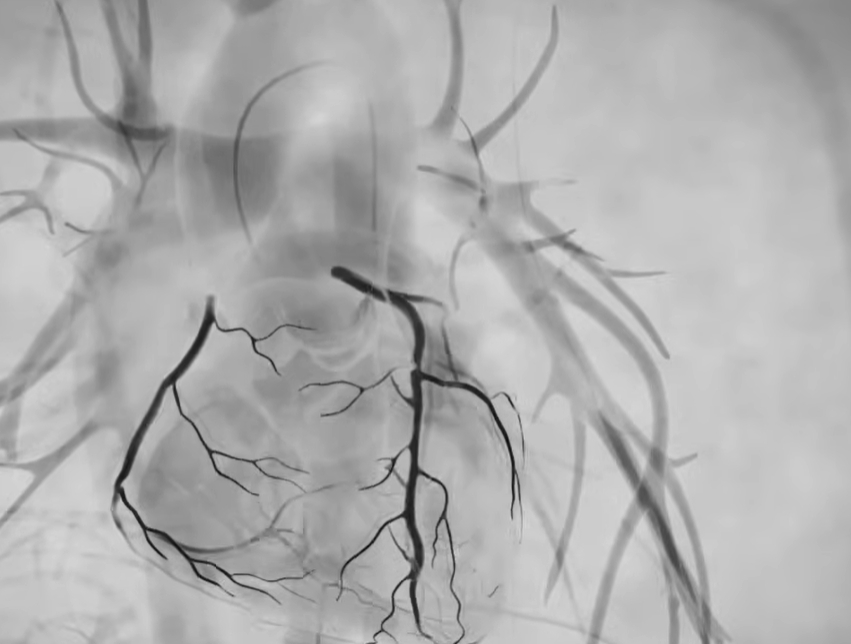

단순한 초음파나 CT와 달리, 조영제를 혈관 안에 넣어 막힘 위치와 정도를 실시간 영상으로 확인하기 때문에 협심증·심근경색 진단의 표준 검사로 사용됩니다. 증상이 애매할수록, 검사 결과가 치료 방향을 크게 좌우하기 때문에 중요한 의미를 갖습니다.

검사는 보통 손목(요골동맥)이나 사타구니 혈관을 통해 가느다란 관을 넣어 심장 혈관까지 이동시킨 뒤, 조영제를 주입하며 X-ray로 촬영합니다.